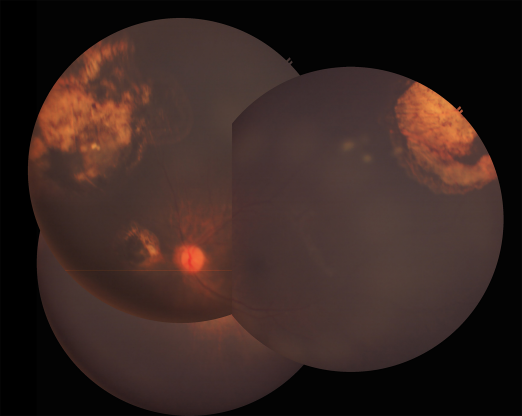

Combined intravenous chemotherapy with focal therapy (thermotherapy and cryotherapy) resulted in regression of the retinal tumors of the left. Partial response of the vitreous seeds was seen, but sphere seeds persisted over the superotemporal tumor and at the inferior periphery (Figure 1 [Fig. 1]). Intravitreal injection of melphalan 20 µg/0.05 cc was performed at the inferotemporal midperiphery (4 o’clock) with cryotherapy (triple freeze-thaw) of the injection site, following the procedure described by Shields et al. [8]. The patient received 2 cycles of injection 6 weeks apart, the first concurrent with the 6th cycle of systemic chemotherapy, and the next 6 weeks thereafter.

Figure 1: Fundus photo montage showing persistent sphere vitreous seeds overlying the tumor superotemporally and at the inferior periphery of the left eye